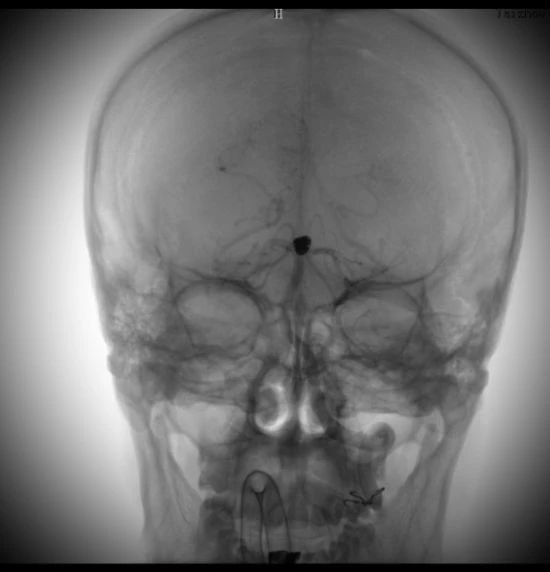

動脈瘤在這里↓↓↓

術(shù)中造影顯示的顱內(nèi)動脈瘤,大家不要小看它,它要是破裂了,可是會要人命的。所以顱內(nèi)動脈瘤又稱為腦子里的定時炸彈。

術(shù)后的動脈瘤長這樣。因為動脈瘤里填充了彈簧圈,所以在X線照射下整體看起來是黑色的